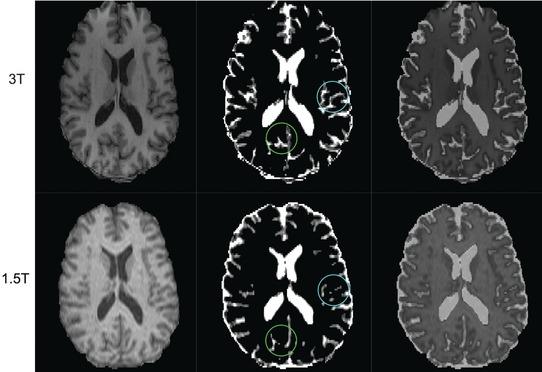

Whole brain atrophy is a putative outcome measure in monitoring relapsing-remitting multiple sclerosis (RRMS). With the ongoing MRI transformation from 1.5T to 3T, there is an unmet need to calibrate this change. We evaluated brain parenchymal volumes (BPVs) from 1.5T versus 3T in MS and normal controls (NC).

BPV-1.5T was higher than BPV-3T [mean (95% CI) + 45.7 mL (+35.3, +56.1), P < .00001], most likely due to improved tissue-CSF contrast at 3T. BPV-3T showed a larger volume decrease and larger effect size in detecting brain atrophy in MS versus NC [-74.5 mL (-126.5, -22.5), P = .006, d = .92] when compared to BPV-1.5T [-51.3.1 mL (-99.8, -2.8), P = .04, d = .67]. Correlations between BPV-1.5T and EDSS (r = -.43, P = .027) and BPV-3T and EDSS (r = -.49, P = .011) and between BPV-1.5T and T25FW (r = -.46, P = .018) and BPV-3T and T25FW (r = -.56, P = .003) slightly favored 3T. BPV-cognition correlations were significant (P < .05) for 6 of 11 subscales to a similar degree at 1.5T (r range = .44-.58) and 3T (r range = .43-.53).

Field strength may impact whole brain volume measurements in patients with MS though the differences are not too divergent between 1.5T and 3T.